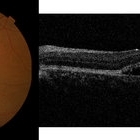

Behcet's Disease Behcet's DiseaseMar 13 2013 by Hamid Ahmadieh, MD OCT of the right eye of a 23-year-old man with retinal vasculitis and branch retinal vein occlusion (BRVO) due to Behcet's disease . Photographer: Solmaz Shahmohammad, Negah Eye Center, Tehran Imaging device: Topcon OCT Condition/keywords: branch retinal vein occlusion (BRVO), optical coherence tomography (OCT), retinal vasculitis